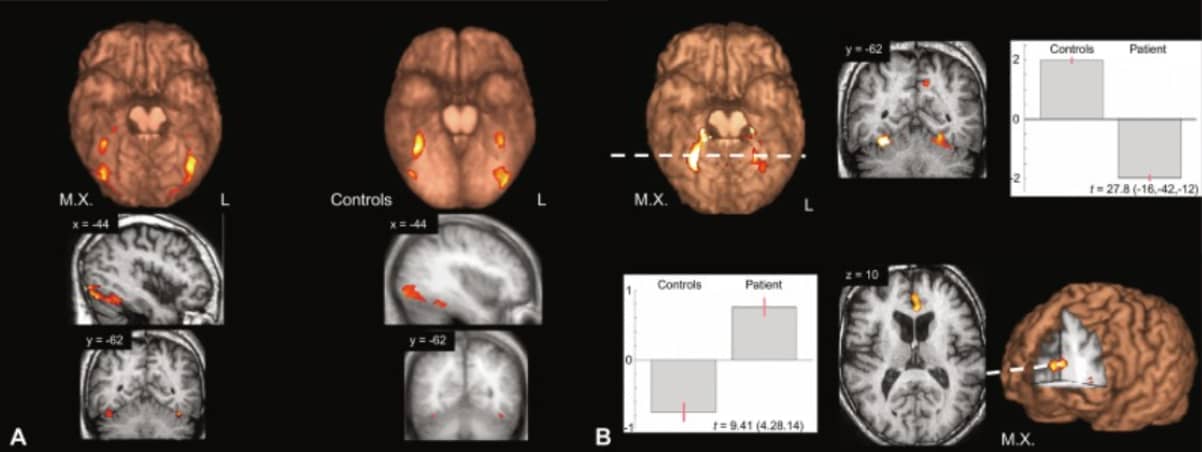

For example, in chapter 15 of the Handbook of Clinical Neurology, Rebecca Keogh and her co-authors discuss the case of MX.

A professional who used to visualize well suddenly found himself a-visual. He could no longer “enter” the novels he read, experience dreams visually, or visually recall faces of friends.

In his brain scans, researchers noted “hypoactivation of his anterior cingulate gyrus,” which means they were underperforming.

Note: MX could still experience mental imagery. It just wasn’t experienced visually. These findings led researchers to come up with terms like “blind imagination” and “blindsight.”